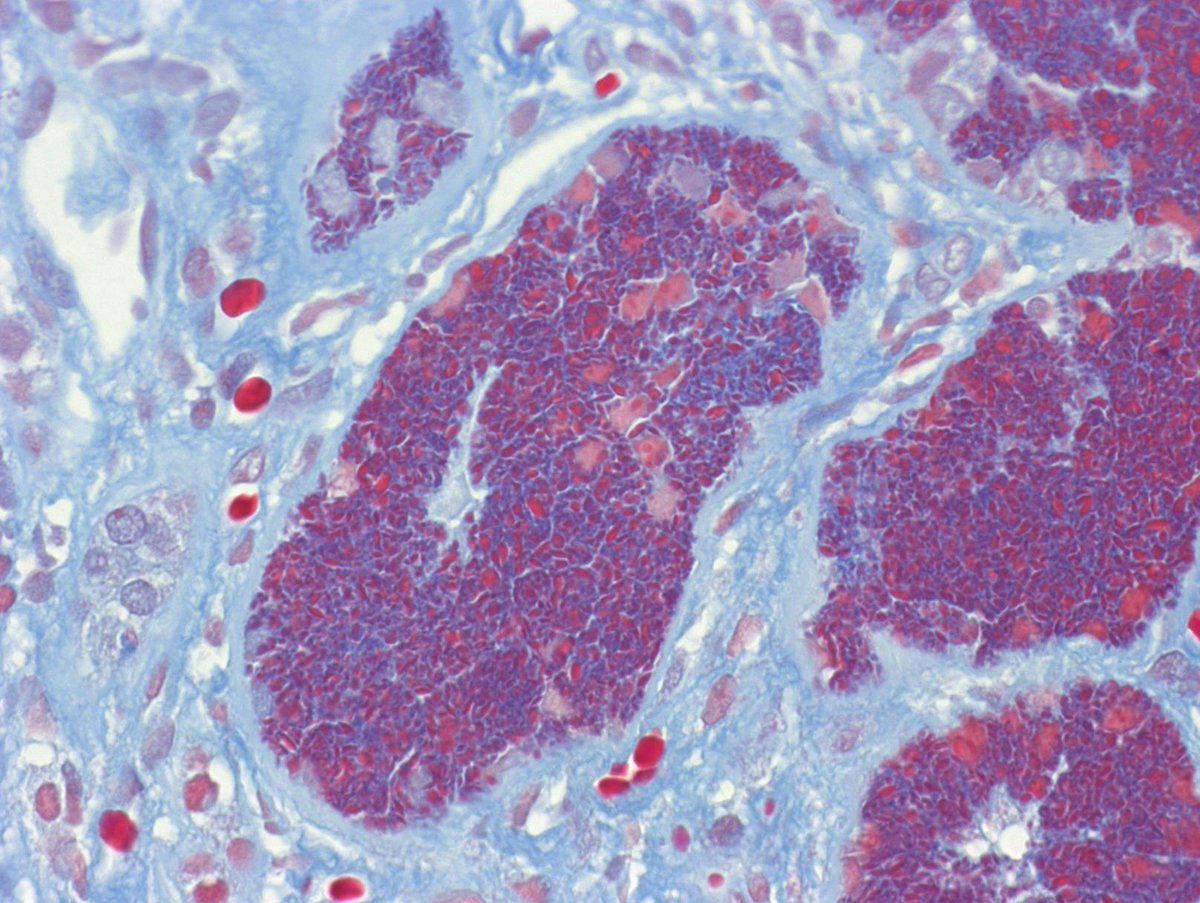

Long weekend often brings urgent cases. Here is one that was STATed, ended up showing anti-GBM GN. Diffuse crescents (nearly 100%). Linear IgG. #RenalPath